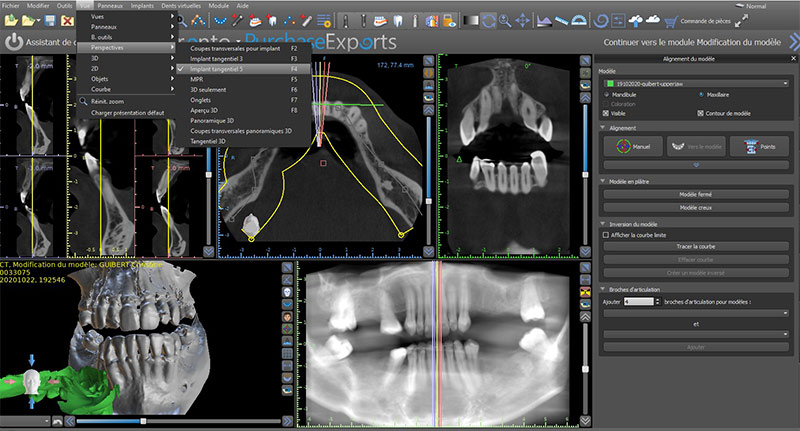

Cinq différentes fenêtres vont possiblement s’ouvrir simultanément, une coupe transversale, une coupe sagittale, une coupe axiale, la courbe panoramique et une vue 3D.

Fig. 06 : perspective, implant tangentiel 5.

Nous pouvons alors commencer notre planification. Nous allons utiliser principalement 5 panneaux nécessaires à la réalisions du guide chirurgical : surfaces, alignement du modèle, liste des dents, liste des implants, fabrication du guide.

Fig. 07 : panneaux à sélectionner.